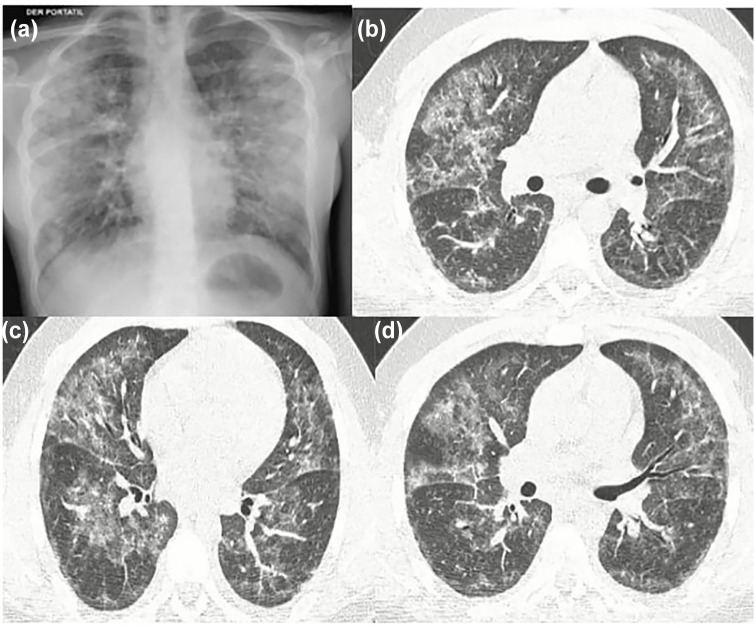

The respiratory impact of e-cigarette usage, also known as vaping, emerged as a significant healthcare issue in 2019. This concern arose due to the sharp rise in cases of e-cigarette or vaping-associated lung injury (EVALI) among adolescents and young adults. Now, systemic manifestations have been described. We present the case of a 39-year-old male patient who had been vaping for 5 years and developed EVALI associated with multiple severe complications, including acute myocardial infarction, metabolic acidosis, acute kidney injury and sepsis-like syndrome, requiring hospitalization in the critical care unit. Every day, reports of patients with systemic complications due to the use of e-cigarettes are becoming more frequent. Therefore, it is crucial for clinicians to be aware of this condition and to consider whether vaping truly constitutes a safe alternative to combat smoking.